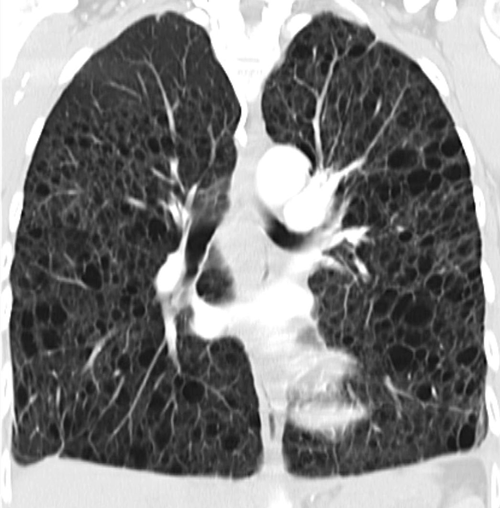

Bei der Lymphangioleiomyomatose kommt es zur unkontrollierte Proliferation glatter Muskelzellen. Bei der Lymphangioleiomyomatose kommt es zur unkontrollierte Proliferation glatter Muskelzellen. © wikimedia/Nephron